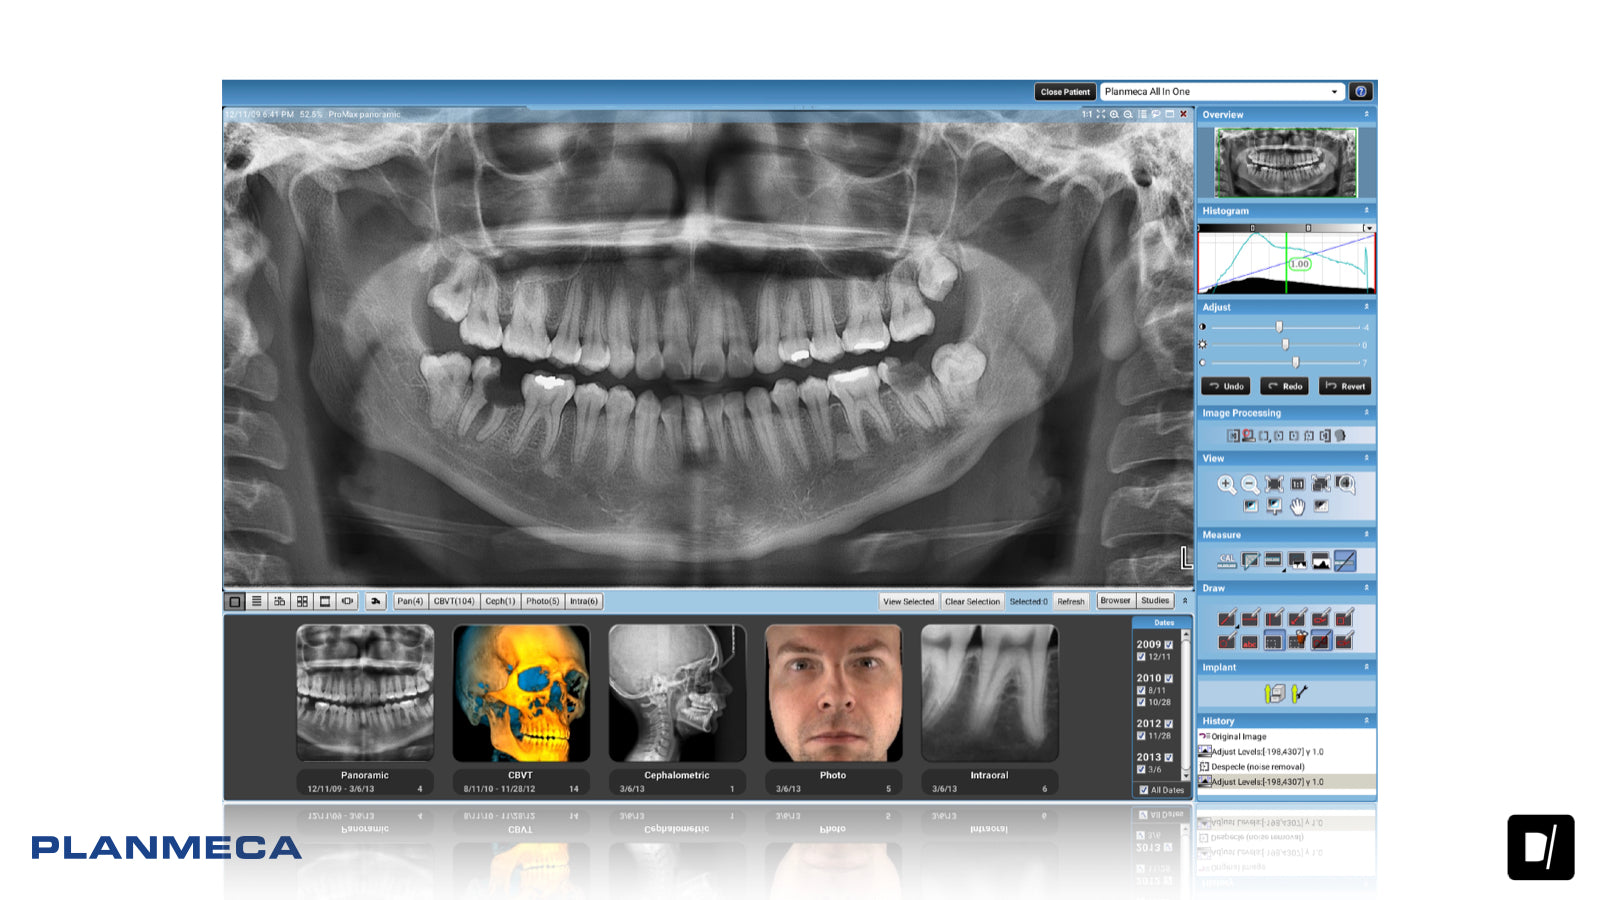

• Planmeca ProMax® 2D es un moderno y completo equipo de radiología oral para el procesamiento de imágenes maxilofaciales. Sus principios de diseño y funcionamiento se basan en las investigaciones científicas y tecnológicas más recientes. Las unidades son capaces de satisfacer incluso las necesidades más exigentes de la radiología dental moderna.

Las unidades de procesamiento de imágenes panorámicas Planmeca ofrecen una avanzada y versátil experiencia de imágenes 2D. Desde el posicionamiento flexible del paciente hasta las innovaciones creativas y la alta calidad de la imagen, representan las imágenes dentales 2D en su máxima expresión.

Gran facilidad de utilización

Todas nuestras unidades de procesamiento de imágenes panorámicas disponen de una interfaz gráfica de fácil uso que contribuye a que el trabajo de procesamiento de imágenes fluya sin problemas en cualquier situación. Puede aprovechar el posicionamiento del paciente en vista completa con luces de posicionamiento de láser triple, así como ofrecer una conveniente entrada lateral para sus pacientes puedan acceder cómodamente.